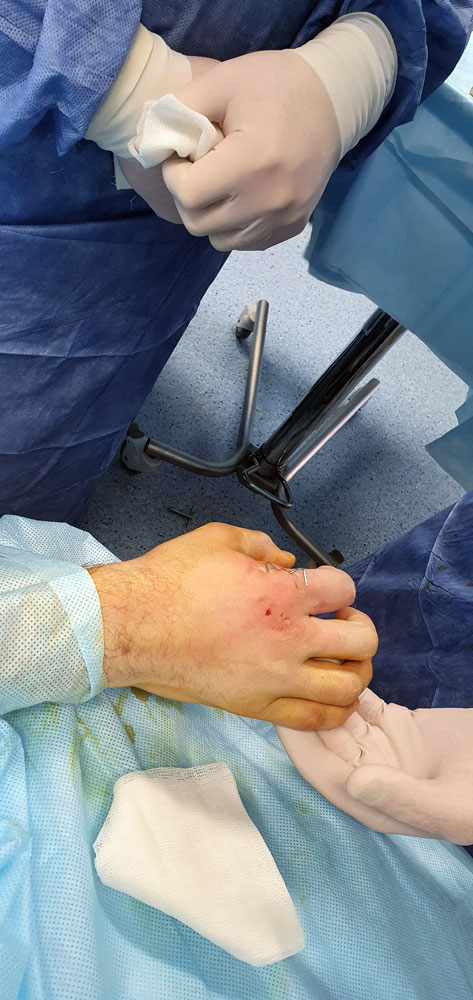

Врачи Пироговского Центра продолжают совершенствовать современные медицинские технологии